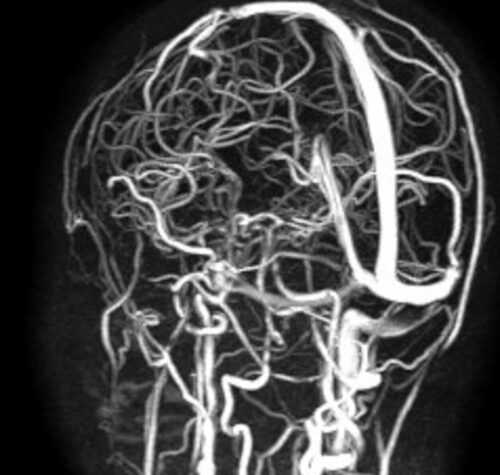

Una bambina di 10 anni ha recuperato completamente la vista dopo un complesso intervento eseguito al Policlinico di Bari, al termine di un percorso diagnostico e terapeutico che ha coinvolto…